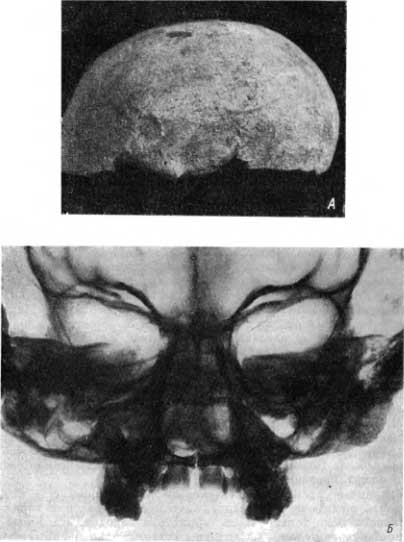

На одном из черепов в лобной кости над левой надбровной дугой обнаруживается дефект, круглой формы, в виде ямки, с хорошо выраженным костным валом (рис. 99, А). На рентгенограмме виден поверхностный дефект кругловатой формы. Следов травматических изменений нет. Костный препарат и рентгеновская картина характерны для гуммы черепа.

Рис. 99. А — сифилитическая гумма на лобной кости; Б — уродство «волчья пасть» у ребенка.

На другом черепе на левой теменной кости обнаруживаются разлитой остеопериостит и несколько деструктивных участков на почве гумм.

Заслуживает некоторого внимания случай уродства на скелете ребенка, достигшего того возраста, когда происходит смена резцов. На этом черепе и сделанных рентгенограммах (рис. 99, Б) хорошо прослеживается врожденная расщелина в области альвеолярного отростка верхней челюсти и в области твердого нёба (так называемая волчья пасть).